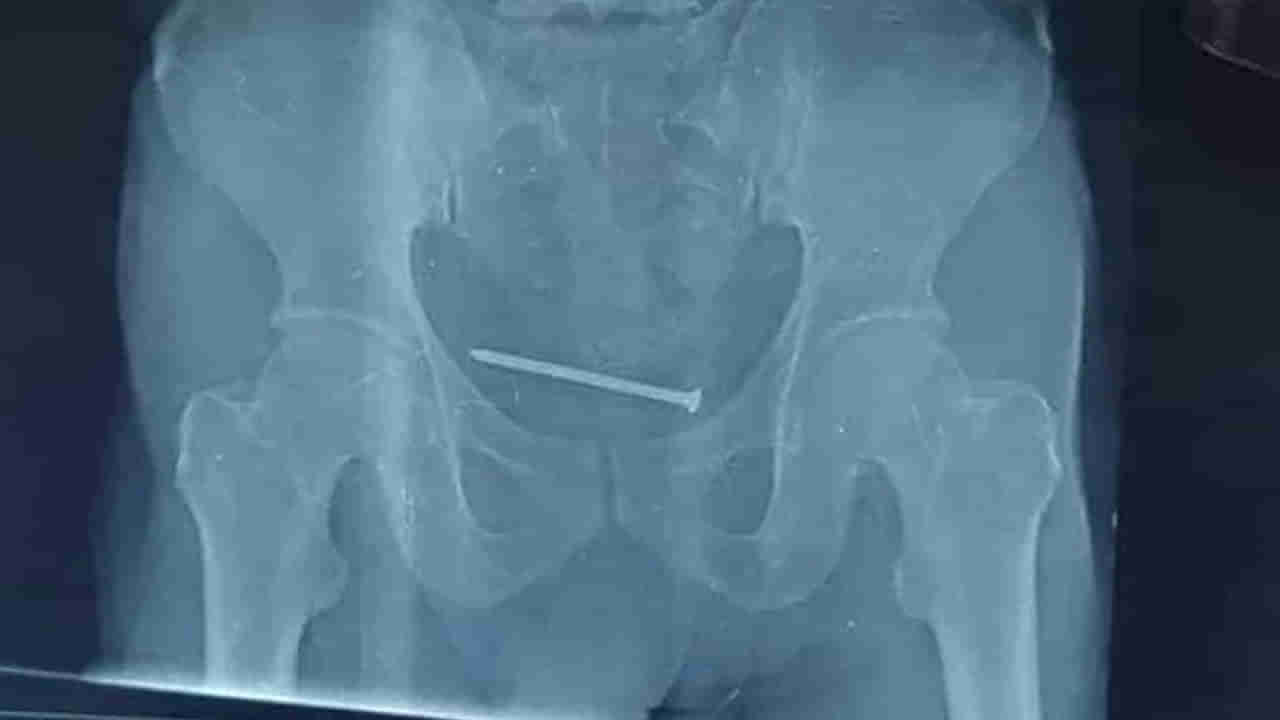

ఓ వ్యక్తి మూత్రాశయంలో తీవ్రమైన నొప్పితో ఆస్పత్రికొచ్చాడు. అక్కడున్న డాక్టర్లు అతడికి పలు టెస్టులు నిర్వహించి.. ఎక్స్రే తీయించారు. అనంతరం వచ్చిన రిపోర్ట్స్ చూసిన వాళ్లు ఒక్కసారిగా కంగుతిన్నారు. ఎక్స్రే రిపోర్టులో సదరు వ్యక్తి మూత్రాశయంలో 10 సెంటీమీటర్ల మేకు ఉన్నట్లు గుర్తించారు. ఈ ఘటన మధ్యప్రదేశ్లో చోటు చేసుకుంది. ఇంతకీ అసలు కథేంటంటే..

వివరాల్లోకి వెళ్తే.. మధ్యప్రదేశ్లోని భింద్ జిల్లాకు చెందిన జాగ్రామ్ అనే వ్యక్తి.. స్థానికంగా ఉన్న జిల్లా ఆస్పత్రికి.. మూత్రాశయంలో తీవ్రమైన నొప్పితో చికిత్స చేయించుకునేందుకు వెళ్లాడు. అక్కడున్న డాక్టర్లు అతడికి పలు టెస్టులు నిర్వహించారు. అనంతరం ఎక్స్రే తీయగా.. 10 సెంటీమీటర్ల మేకు ఒకటి సదరు వ్యక్తి మూత్రాశయంలో ఉన్నట్లు డాక్టర్లు గుర్తించారు. సుమారు గంట పాటు శస్త్రచికిత్స నిర్వహించిన డాక్టర్లు.. అతి కష్టం మీద ఆ మేకును బయటికి తీశారు. ప్రస్తుతం సదరు వ్యక్తి ఆరోగ్యం నిలకడగానే ఉందని డాక్టర్లు తెలిపారు. ఇదిలా ఉంటే.. ఇంతకీ అసలు ఆ మేకు ఎలా లోపలికి వెళ్లిందో ఆ వ్యక్తి తెలియదట. కాగా, ఇలాంటి ఘటనలు తరచూ జరుగుతుండటం గమనార్హం.